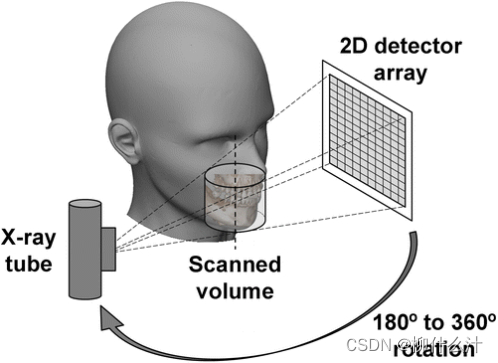

经典ct重建的图像采集

x射线管和探测管同时围绕旋转轴移动

虽然每种cbct设备的基本采集原理是相同的,但在比较采集方法和参数时,重要的差异是显而易见的。首先可以区分的是脉冲式和连续式曝光,脉冲和连续曝光都容易受到探测器滞后的影响,但脉冲更可能表现出更好的空间分布率,因为运动效应减少。其次是旋转角度,大多数cbct扫描仪都是360°获得投影,但是由于机械障碍,全旋转是无法做到的,所以会采取半旋转,此时可以重建出完整的FOV.但是由于头颈部对辐射敏感分布的器官分布不均匀,如骨组织的体积自我衰减和软组织的难以显影。就图像质量而言,部分旋转往往会降低整体图像质量,根据毫安的不同,180°旋转方案比360°方案会导致噪音的轻微或更明显的增加,与较短的扫描相关的采样减少也会导致较短的扫描的图像质量下降(即使总的扫描毫安数是相同的),明显的是与较少的投影数相关的视图混叠效应略有增加。视图混叠效应往往是次要的,而短扫描与360°扫描的全面特征,以及起始角度对图像质量的影响(或没有影响)还没有得到全面评估。